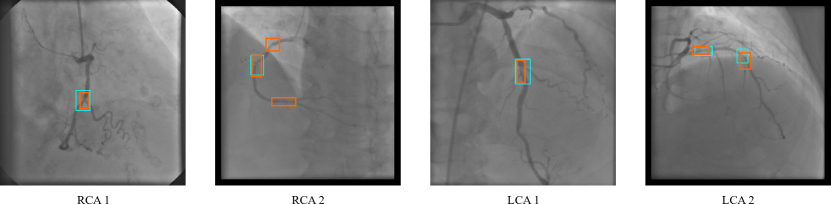

Figure 4: Stenosis detection examples in validation set for RCA and LCA viewing angles with cyan bounding boxes denoting ground truth annotations and orange representing the estimated ones.

Our baseline (B) is defined as having all frames from the full radio-opaque contrast interval included in training. Performance is evaluated only in reference frames. In attempts to improve the model’s capacity at differentiating positive examples (stenosis) from negative ones (background/healthy coronaries), experiments were made including background (BG, frames without any contrast) and healthy coronary frames (NL) to the RCA and LCA models.

Cong et al. 0.60 - - -

We compare the performance of all our models against themselves and with previous work. Table 3 shows that our model outperforms the model of Cong et al. [4]. From visual validation of the model’s performance (see Figure 4), it is possible to observe that it performs better in frames with only one stenosis. However, in cases where more than one stenosis is present, the model struggles at the detection in its entirety. Nevertheless, the models can detect several stenoses per frame even with hard examples (iFR above threshold), achieving good performances. The results show that our variations on the base model improve the performance on the LCA, but the addition of more true negative examples on the RCA did not boost performance.